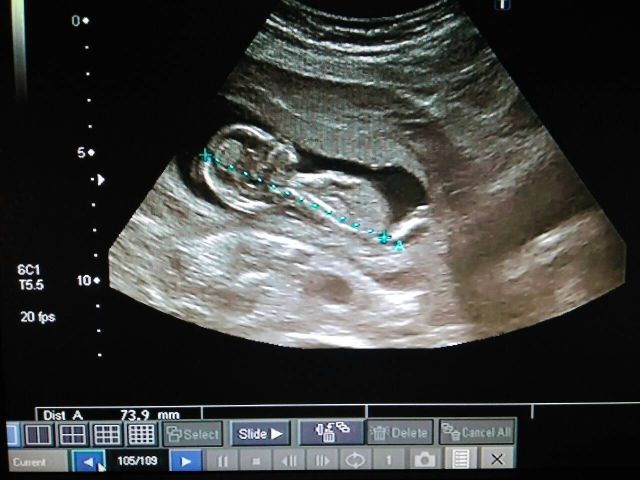

Нам сейчас 13,3 недельки, сегодня была на УЗИ КТР - 80мм, ТВП- 2,2, СБ162 удара в минуту. А еще нам врач сказал, что у нас мужчина!!!! 😍 😍 😍 😘 😘 😘